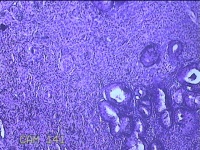

宫颈赘生物

性别

女

年龄

49岁

临床诊断

人乳头瘤病毒感染

一般病史

宫颈HPV阳性TCTLSLL

标本名称

大体所见

灰白粉红色肿物1.2x0.8x0.2cm两个,表面光滑。